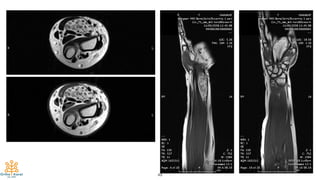

Case #3

53

79-year-old, M

8-cm-mass at forearm for 1 year

No pain

54

55

56

57

Final Diagnosis:

Candidiasis